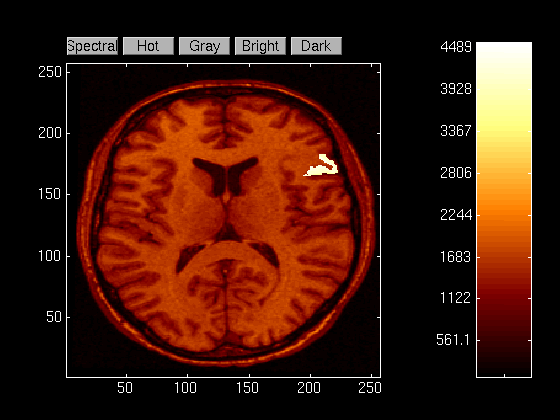

Now that we have the mask, we can view the painted image superimposed on the underlying structure. Note that we must reshape the mask before adding it to the variable MRI since MRI is a column vector image, and the mask is a square matrix.

viewimage (reshape(mask,length(MRI),1) + MRI);